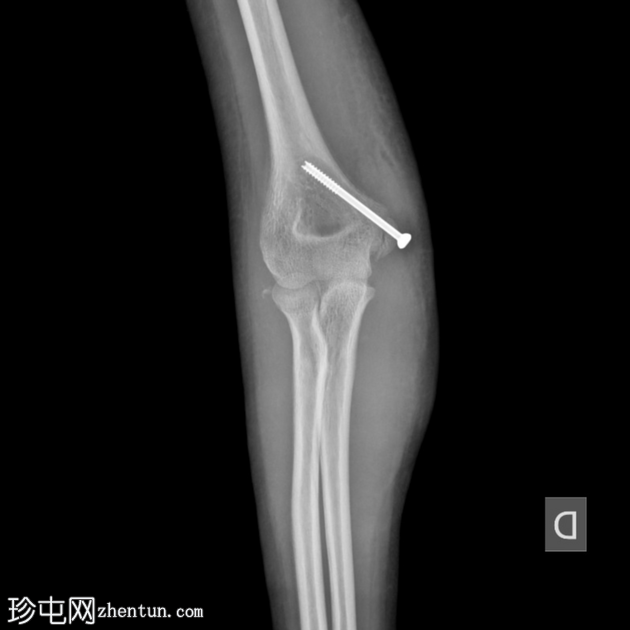

X线片

3.png

正位片

4.png

侧位片

两个投照角度均显示肘关节复位良好。

复位后,骨碎片被明确识别为未完全骨化的内上髁骨折。

肘关节内仍有积液。